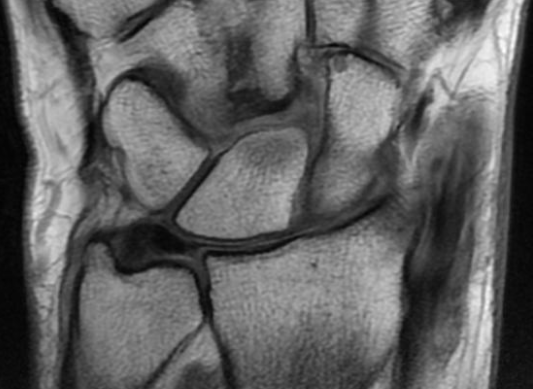

Anatomie